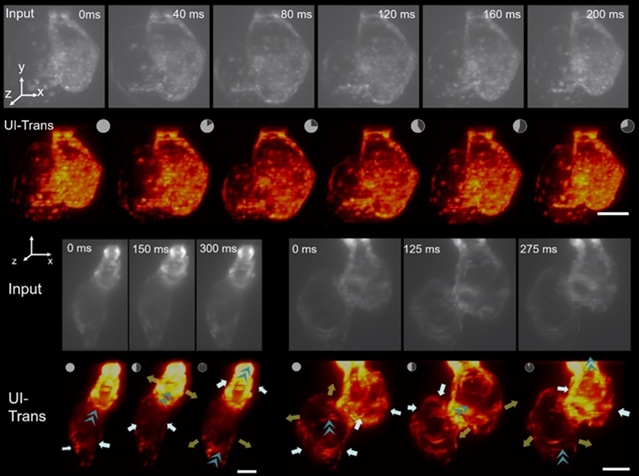

通过在离体斑马鱼心脏数据集上训练的UI-Trans模型恢复了活体斑马鱼心跳三维影像。图3展示了不同发育阶段(胚胎,30小时;发育阶段48小时和晚期心脏发育阶段,120小时)斑马鱼的心跳动态影像的恢复图像。经过UI-Trans增强后,心室能够清晰地从背景中分离出来,信噪比显著提高。

值得一提的是,即使在离体训练集图像中没有任何早期胚胎时期的心脏影像数据,UI-Trans仍能有效提升发育早期活体斑马鱼胚胎的心跳影像的图像质量。

上述成果表明,该方法能够实现不同发育阶段完整斑马鱼心脏的高质量快速4D成像,为心脏研究带来了新的视角。

图3. 使用UI-Trans进行活体斑马鱼心脏影像恢复。48h.p.f. (上)、30h.p.f. (左下)和120 h.p.f.(右下)斑马鱼心脏跳动影像的不同时间点恢复前后对比图(灰色:恢复前,橙色:恢复后)。